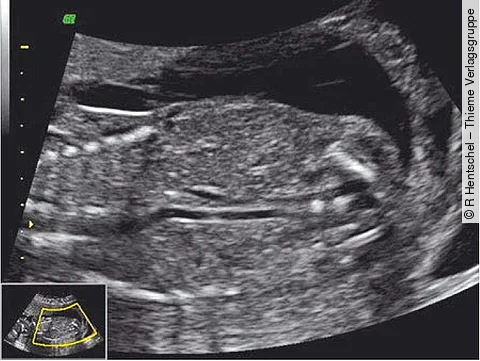

Letztes TrimenonSchwangere sollten am besten seitlich schlafen

Je weiter die Schwangerschaft fortschreitet, desto mehr Gewicht muss die Mutter in spe mit sich tragen und auch zur Schlafenszeit mit ins Bett nehmen. Wie eine Schwangere dabei auf der Matratze liegt, hat Einfluss auf die Vitalität ihres Babys. Denn wenn sie auf dem Rücken liegt, wird das Kind stiller – voraussichtlich weil es einen leichten…